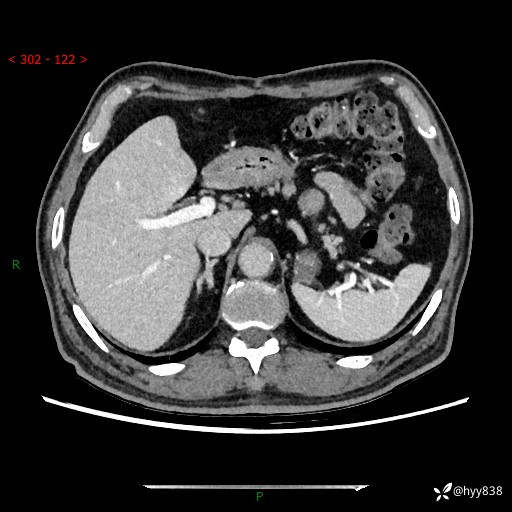

69岁/男,四肢无力3月余。胰腺囊实性占位,渐进性强化---结果公布~

【患者信息】:69岁/男

【主诉】:四肢无力3月余。

【现病史及既往史】:患者3月前无明显诱因出现四肢乏力,伴有口干、多饮、多尿等症状,无畏寒、发热、恶心、腹痛、腹泻等其他症状,于2024-06-13来我院住院治疗,完善相关辅助检查后,考虑“2型糖尿病”,予以降糖(阿卡波糖片 50mg po tid、德谷门冬双胰岛素注射液 8iu 早餐前 皮下注射)等治疗,口干、多饮、多尿较前缓解,血糖控制可;现仍存在四肢乏力,于2024-08-28来我院门诊就诊,查血钾2.88 mmol/L ,现以“低钾血症”收入我科。 本次起病以来,患者精神、饮食、睡眠良好,二便正常,近3月余体重下降约5kg。

【检查】:胰腺CT平扫+增强